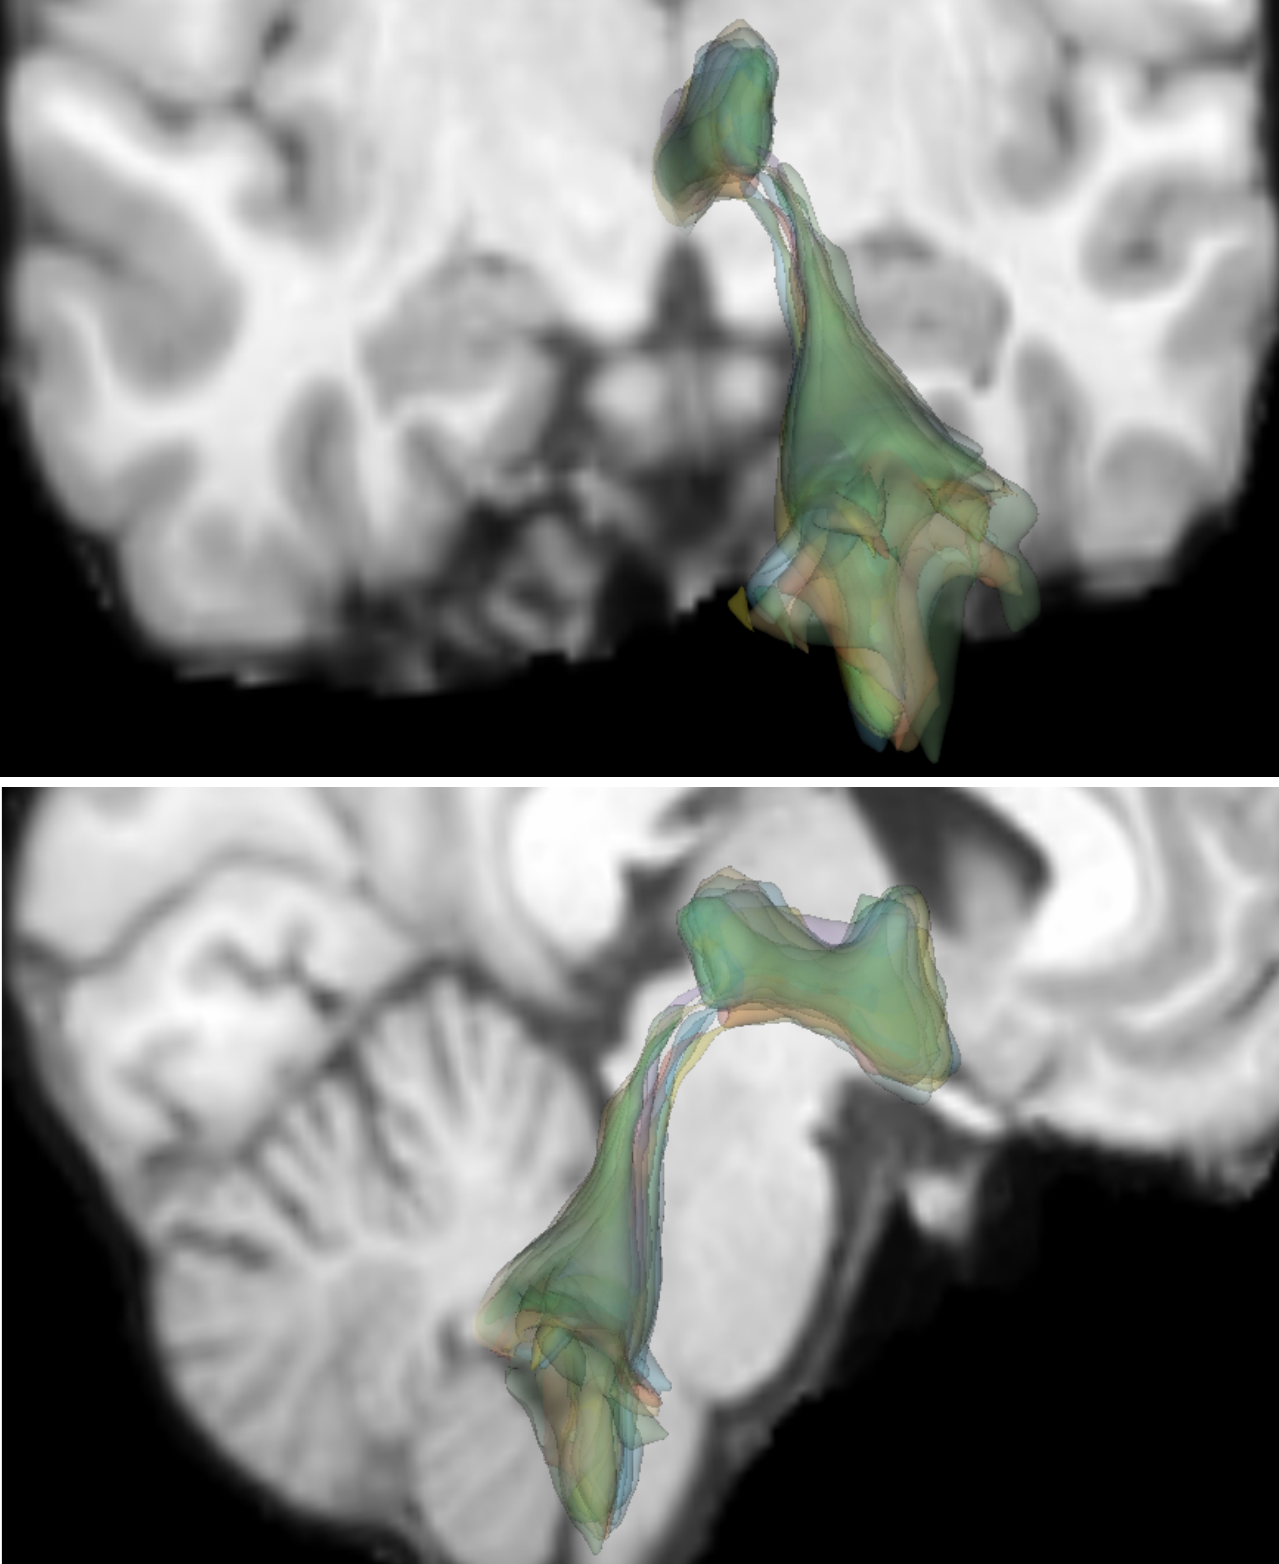

[Spaghetti plots of hippocampus on 2D slices (20 members)]

[3D spaghetti plots of hippocampus]

[3D contour plots of hippocampus]

[Spaghetti plots of ventricles on 2D slices (20 members)]

[3D spaghetti plots of ventricles]

[3D contour plots of ventricles]

5.2 IXI Dataset

Our method can be used to effectively process 3D binary masks using the binary specialization of GPU PID-mean. Examples are shown for the publicly available Information eXtraction from Images (IXI) dataset [antonelli2022medical]222https://brain-development.org/ixi-dataset/. Specifically, we use 400 T1-weighted MRI volumes of size .

For structure-specific analysis, we consider the segmentation labels of the hippocampus (Fig.˜9(a, b, c)) and the third and fourth ventricles (Fig.˜9(d, e, f)). Binary contours of a few members are visualized as spaghetti plots on 2D slices (Fig.˜9(a, d)) and as 3D isosurfaces (Fig.˜9(b, e)). These spaghetti plots reveal the fine structures of the contours but are already cluttered, and, especially for the 3D cases that suffer from severe occlusions.

Clear visualizations are achieved with 3D contour boxplots generated from the PID-mean outputs. Contour boxplots of the hippocampus (Fig.˜9(c)) reveal the high agreement between the envelope of 50% (orange) members and 100% members (blue), and the median member (yellow) shows the representative shape and size of the ensemble. While for the ventricles, contour boxplots (Fig.˜9(f)) show that there is visible space between the envelope of the 50% members and that of the 100% members, the median member reveals the typical ventricles of the ensemble. Regions inside the interior surfaces are small indicating that variations between members are rather large.

PID-mean helps to gain insights into the trends of the complex anatomical structures in the binary contour ensemble. The example demonstrates that PID-mean has the potential for analyzing specific medical problems in cohort studies using ensembles of medical images.